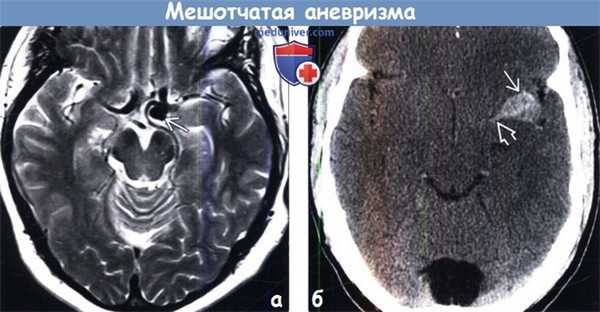

(а) Наиболее частыми локализациями мешотчатой аневризмы (МА) являются ПСоА и область перехода ВСА-ЗСоА. Другими частыми участками локализации мешотчатой аневризмы (МА) являются бифуркация СМА и верхушка основной артерии.

(б) Разрыв аневризмы ПСоА с продолжающимся направленным кверху кровоизлиянием (сосок Мерфи) мешотчатой аневризмы (МА) задней соединительной артерии, а также мелкая аневризма в области бифуркации левой ВСА также представлены на рисунке. Вероятность наличия нескольких аневризм у пациента с выявленной МА составляет 20%. (а) Мужчина 63 лет был найден лежащим на стоянке и доставлен в приемное отделение. Бесконтрастная КТ, аксиальный срез: определяется диффузное субарахноидальное кровоизлияние с формированием фокальной гематомы в передненижнем отделе межполушарной борозды.

(б) КТ-ангиография, проекция максимальной интенсивности, корональный срез: у того же пациента определяется мешотчатая аневризма диаметром 4 мм, располагающаяся кверху от передней соединительной артерии.

(а) Проходимые мешотчатые аневризмы визуализируются на МР-изображениях как округлые гипоинтенсивные участки потери сигнала за счет эффекта потока. Представленная мешотчатая аневризма, локализующаяся в области бифуркации ВСА, обнаружена случайно на Т2-ВИ при МРТ головного мозга пожилого пациента.

(б) Тромбированные мешотчатые аневризмы (МА) могут быть значительно гиперденсными. Этот пациент поступил в приемное отделение по поводу внезапного появления правостороннего гемипареза. При проведении бесконтрастной КТ, как первоочередного исследования при подозрении на инсульт, была выявлена овоидная гиперденсная зона, а также структура в проксимальном отделе левой ВСА, по-видимому, представляющая собой тромб.